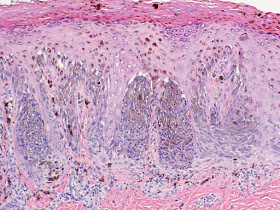

Photomicrographs (courtesy of Deon Wolpowitz, Boston University Skin Path)

Diagnosis: Clinically and dermatoscopically and pathologically, this is a Reed Nevus.